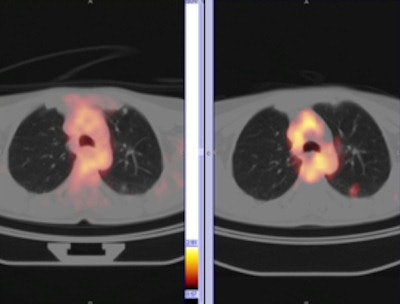

Differences in breathing patterns between CT and PET exam imaging can cause misregistration of pulmonary nodules on fused images, particularly at the lung bases. CT scans of the thorax are generally performed during a breath-hold, while PET images are acquired during tidal breathing. The authors recommend that acquiring CT images of the thorax during quiet respiration will help reduce artifacts.